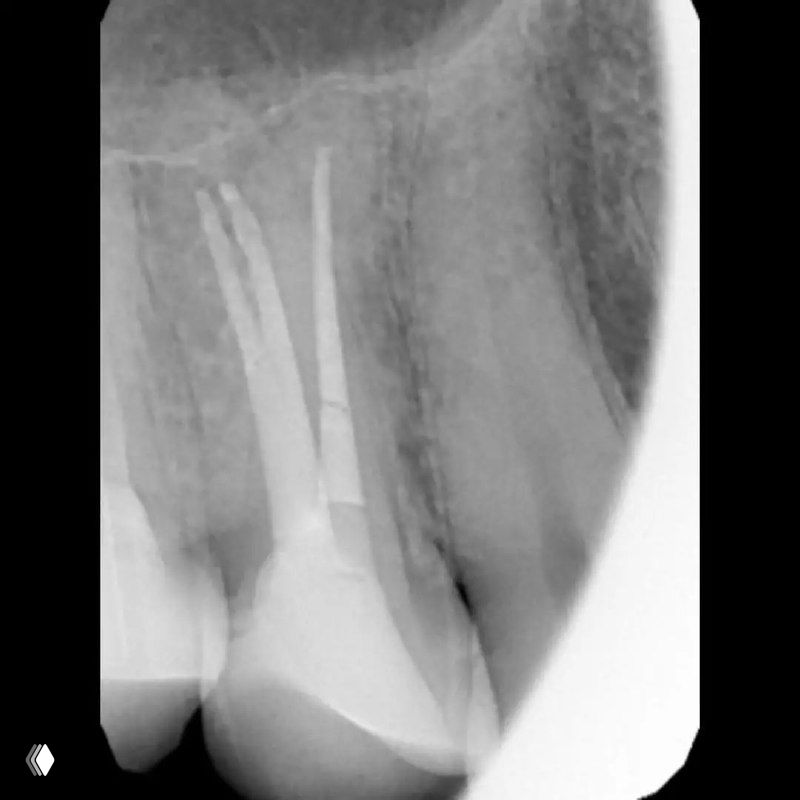

Распространенность: 1 премоляр вч - 3.2%, 2 премоляр вч - 0.4%

На что обратить внимание:

- классическую овальную полость доступа нужно немного расширить в области щёчных каналов в мезио-дистальном направлении

- проводить аккуратное расширение щёчных каналов, так как в области данных корней очень мало дентина (в моём случае расширение 25.04)

- аккуратно латералить без лишнего давления, а для вертикалки использовать самые тонкие плаггеры. А в идеале сделать гибрид.